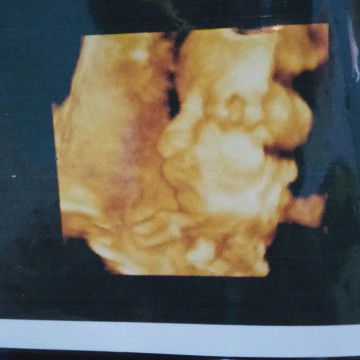

32w

Sudah tak sabar rasanya yaa.. 😁❤️ Doakan kita selalu sehat ya bunda² cantik, semoga di persalinan nanti di lancarkan 🤲